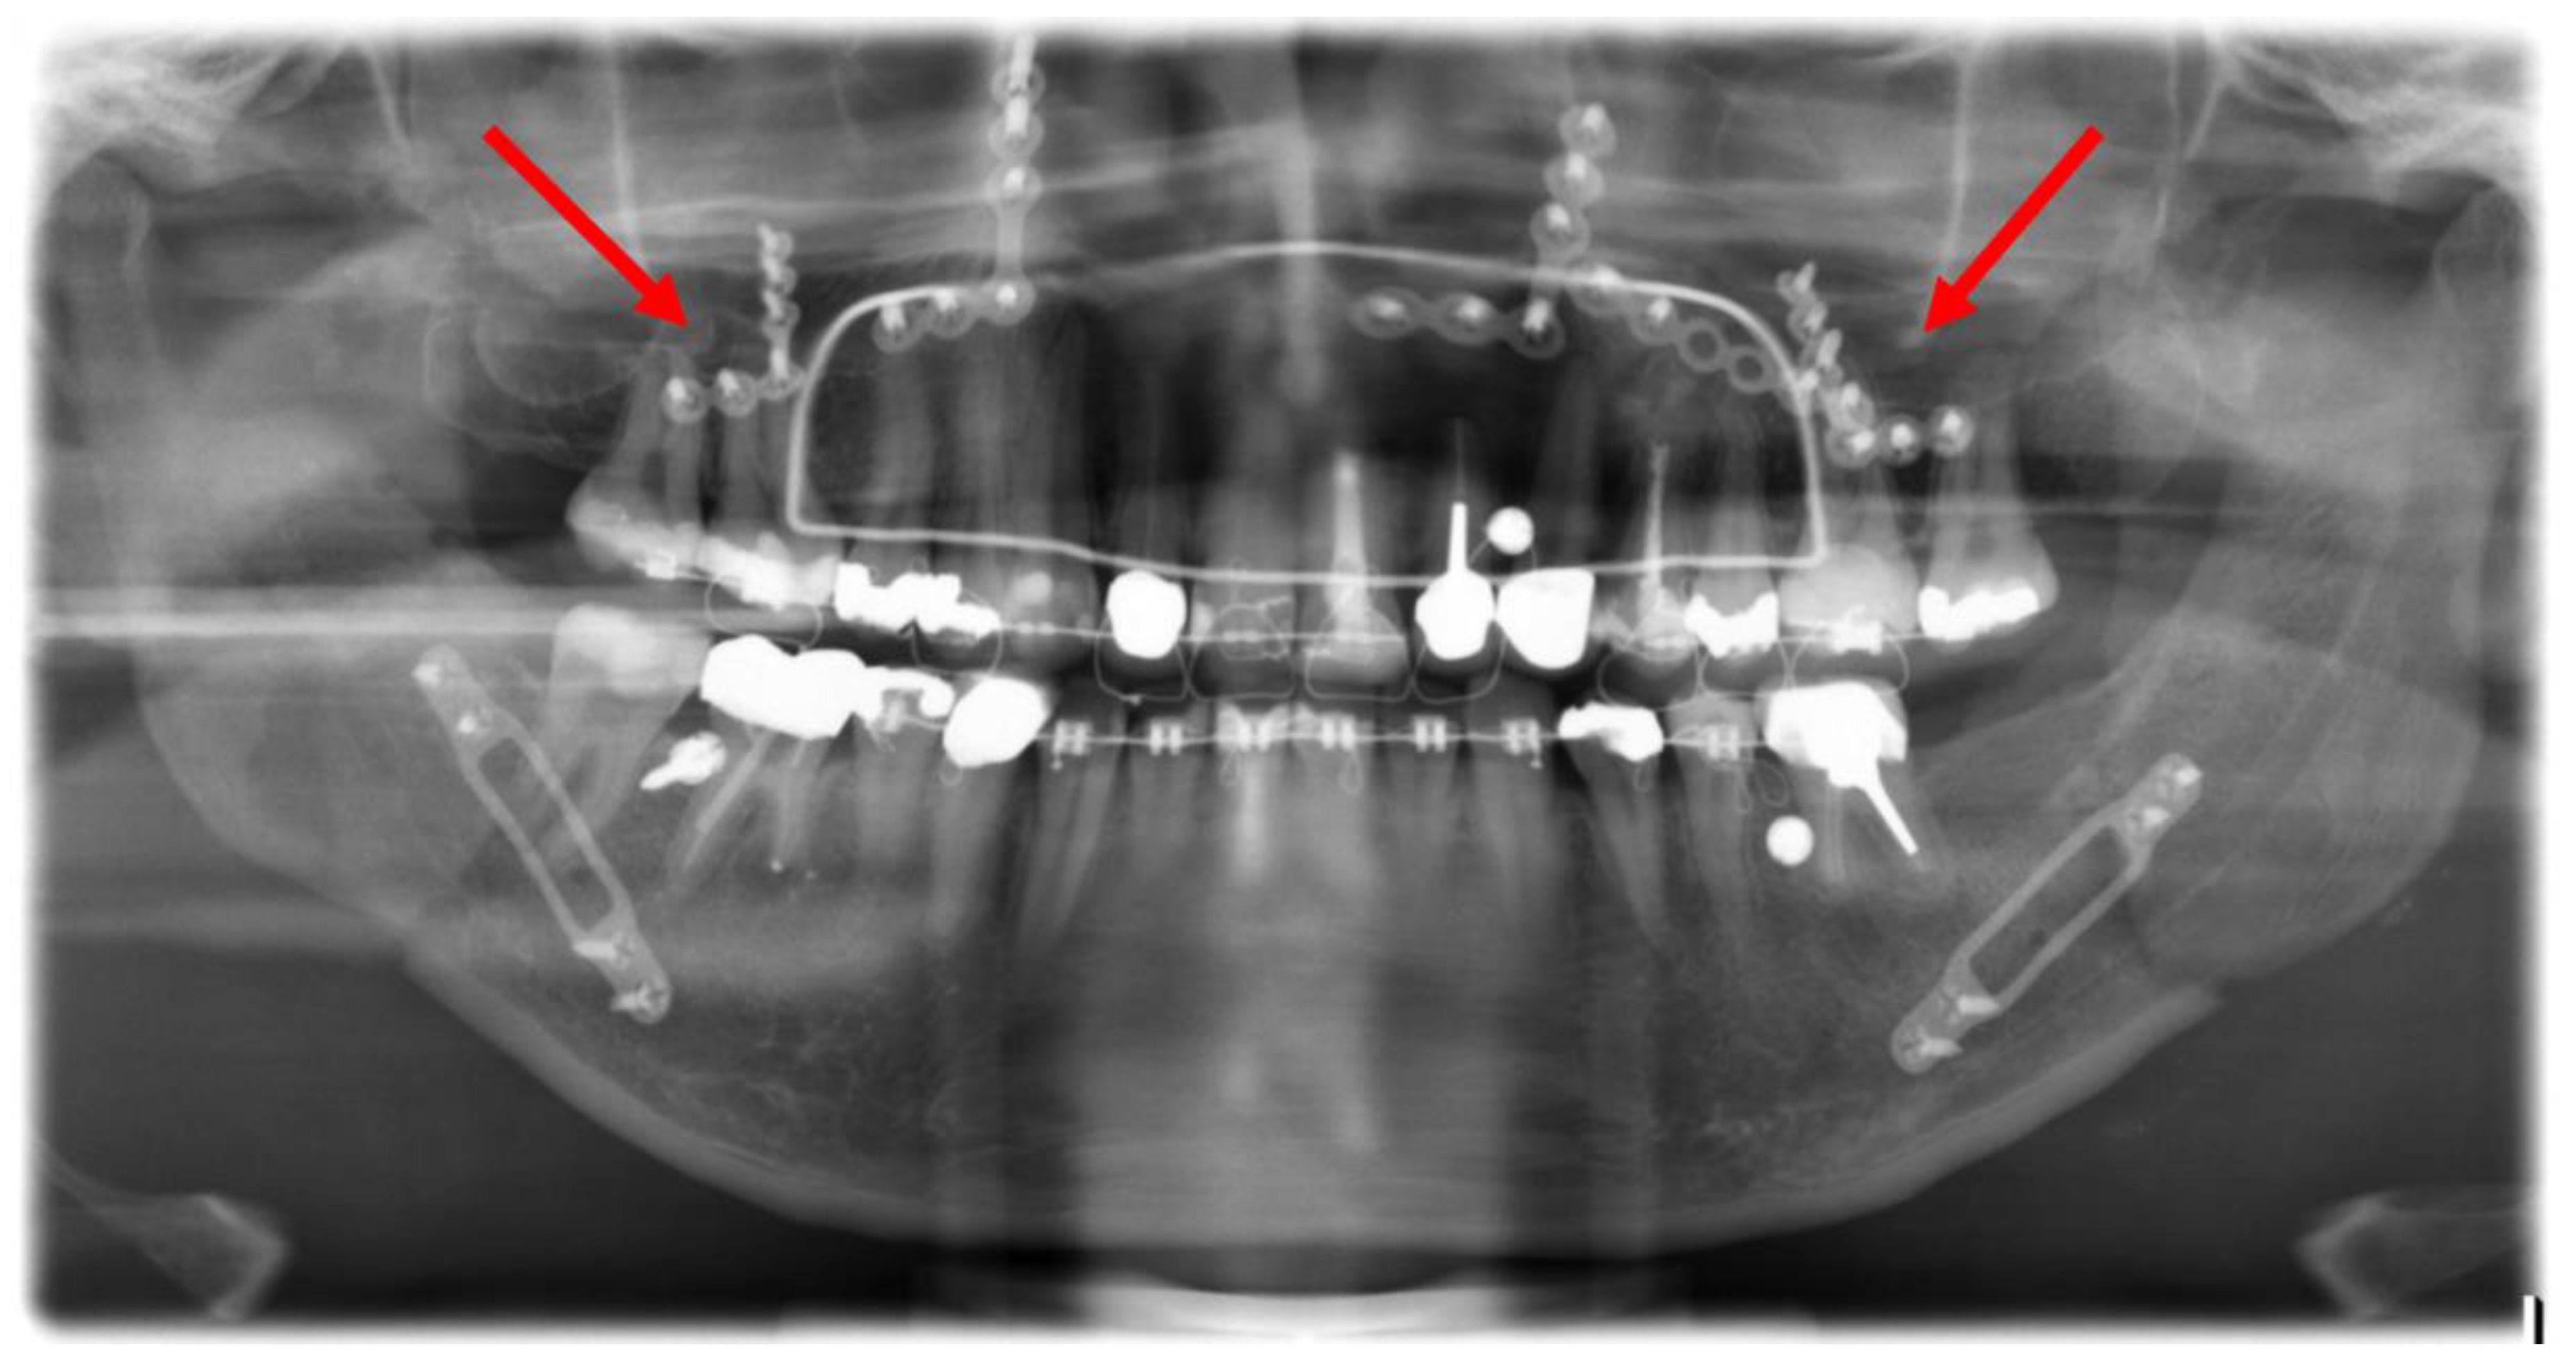

A follow-up of patients with confirmed dental root injuries was conducted at 13 months (median 9.9, min. 6.1, max. 45.5). During this period, none of the injured teeth showed evidence of periapical alterations and no endodontic treatments were performed. Figure 8 presents a case with CT-confirmed dental root injury directly, post-operatively, and after removal of the osteosynthesis material 10.8 months after primary surgery.

Figure 8.

Image (1): Projection of an osteosynthesis screw in the distal root of tooth 36 in the post-operative orthopantomogram after mandibular sagittal osteotomy. Image (2): CT confirmed dental root injury of the distal root of tooth 36 (red arrow). Image (3): Left posterior mandibular region after removal of the osteosynthesis material 10.8 months after primary surgery. The red arrow marks the area of radiologically proven root injury. No apical alterations are shown, and no endodontic treatment had been necessary up to this point.